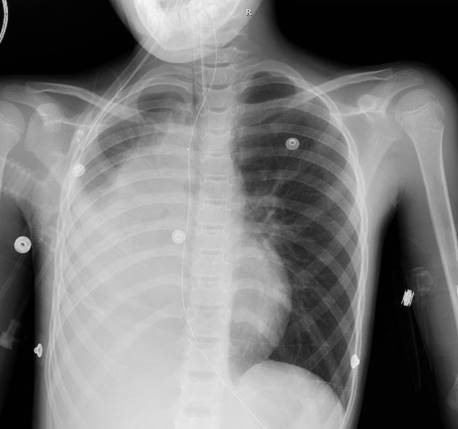

A 9-year-old with pectus excavatum presented to a local hospital with respiratory distress. She awoke 2 days prior to presentation saying that she couldn't breathe and had to throw up. Her sister has asthma, and albuterol at home, so she was given an albuterol treatment and her symptoms improved. She went to school and participated in regular activities. After school, she awoke from a nap with shortness of breath and a high-pitched loud breathing sound. She didn't improve with a second albuterol treatment, so parents brought her to the hospital where her oxygen saturations were in the mid-80s on room air. She received a third albuterol treatment and a chest X-ray was read as a RML pneumonia with tracheal deviation. She was given one dose of ceftriaxone and was transferred to an outside teaching hospital, where she was started on scheduled albuterol. There, pulmonology was consulted and recommended a CT scan, but she needed oxygen while lying flat to maintain acceptable O2 saturation. Flex bronchoscopy was performed, and she was transferred back to their PICU, intubated. The decision was then made to transfer her to St. Louis Children’s Hospital.

• Vital Signs: T 37.6C | HR 110 | RR 33 | BP 119/92 | SpO2 93% on ventilatory support with an FiO2 of 100%

• Pulmonary: Coarse, diminished breath sounds on the right. No audible wheeze or crackle. Pectus excavatum.

Imaging:

A CT scan was obtained…and read as: "Abrupt cut off of the right mainstem bronchus just below the carina without tapering with an apparent enhancing endobronchial mass. Severe volume loss in the right hemithorax and consolidation of the entire right lung that is favored to represent a combination of severe atelectasis and postobstructive pneumonia. No definite mediastinal, hilar, supraclavicular, or axillary lymphadenopathy. Severe pectus excavatum deformity."